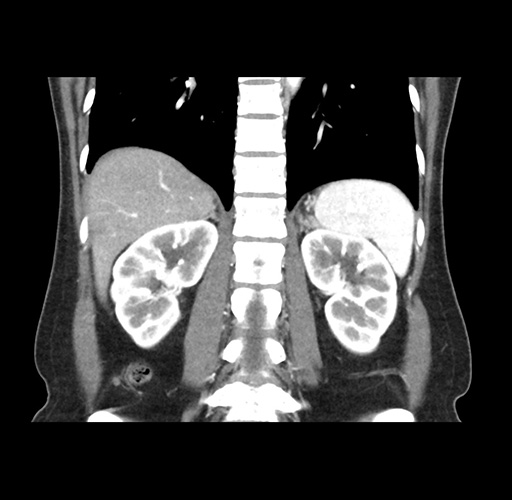

Imaging Analysis

Look through the patient's CT scan to identify any areas of concern for the necessary procedure.

Based on your CT findings, which issue(s) would give reason for "planned slowing down moment(s)" in this case?